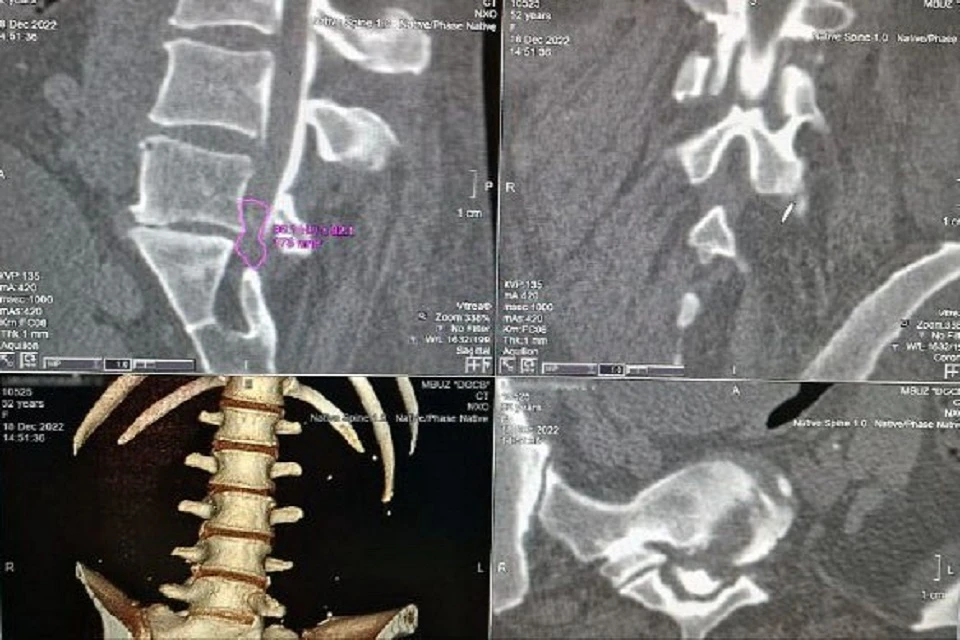

Грыжа паралич

Грыжа паралич 106 фотографий